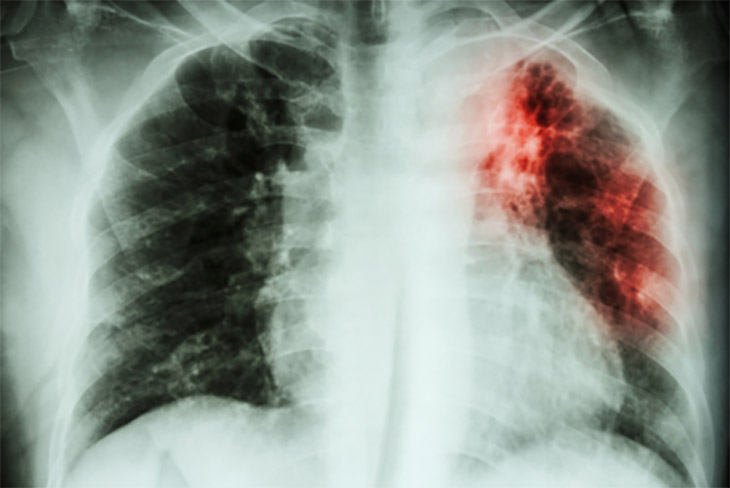

Chest x-ray of a tuberculosis infection in the lung

For centuries tuberculosis, also known as consumption, has killed millions of people around the globe. According to the World Health Organization, TB sickened nearly 11-million people in 2021, an increase of 4.5% from the previous year. Since 2020, tuberculosis has been the second deadliest infectious disease, behind COVID-19.